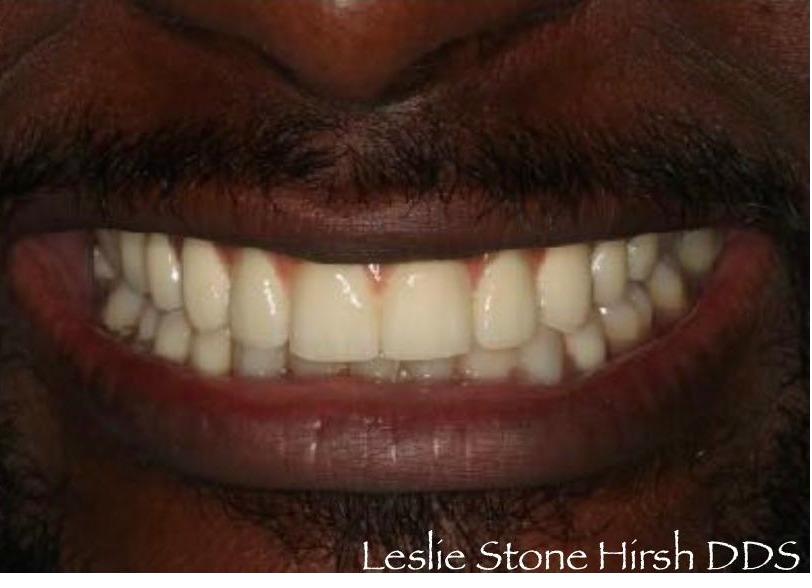

To improve this patient's esthetics, he first had orthodontics to properly align the teeth followed by bleaching. I then replaced the old crowns on his two front teeth with new ceramic crowns to improve the color, contour and esthetics. He was extremely happy with his new smile.

This patient had significant wear and chipping of his teeth. To restore his dental esthetics and function, following orthodontic therapy I fabricated crowns for his front teeth to restore the proper length, contour, and esthetics. He was thrilled with the result of our interdisciplinary care.

To improve this patient's esthetics, after orthodontic treatment we bleached his teeth to brighten his smile. Once we achieved the desired shade I fabricated new crowns to match his other teeth. He was extremely happy with the result!